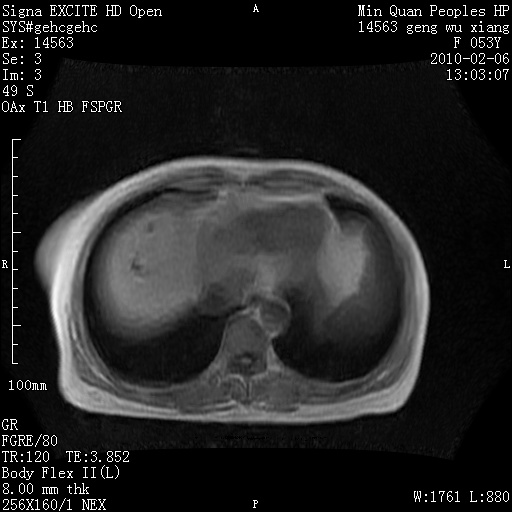

标题: MRI2762:胆道梗阻原因?

f,53y,全身黄染多日。

高位胆道梗阻 胆管癌可能性大

支持 高位胆道梗阻 胆管癌可能性大。